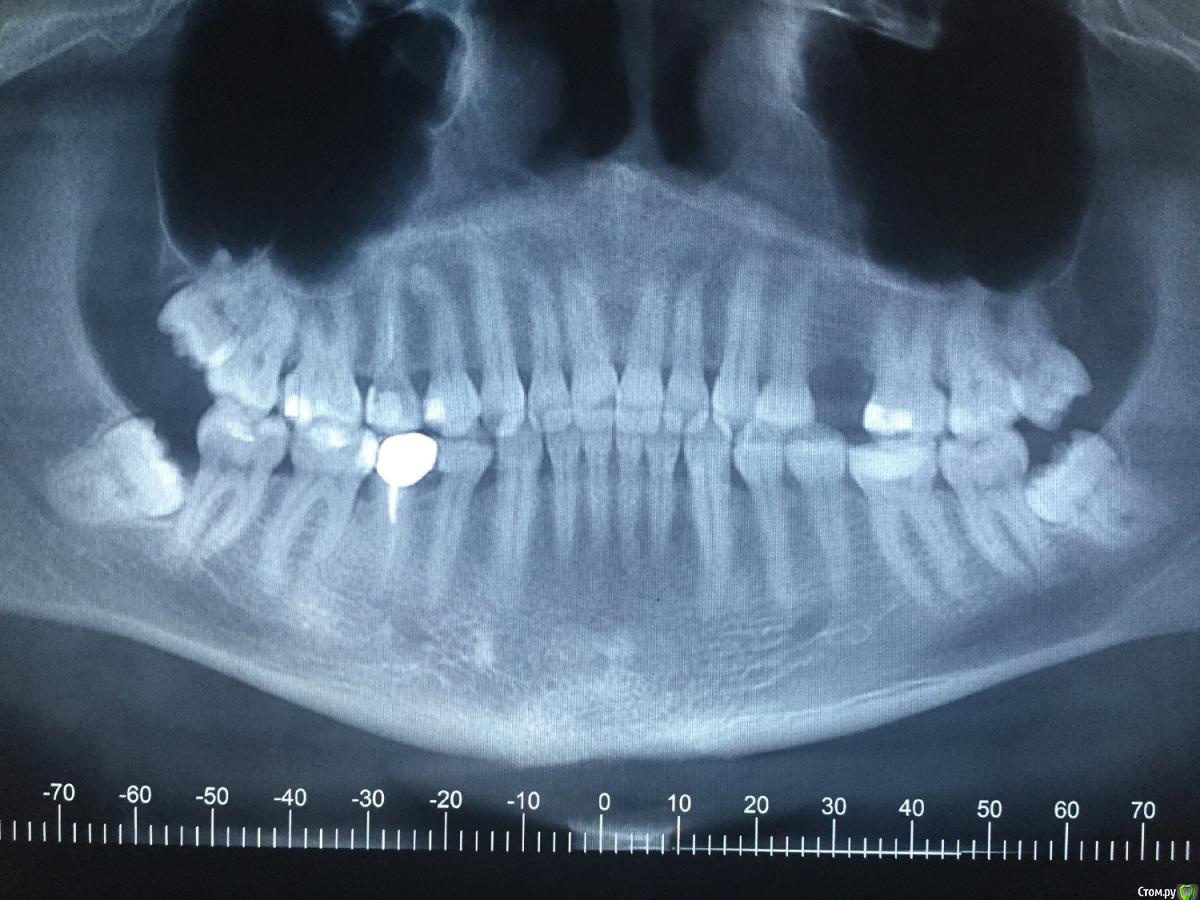

Max_pterovin Опубликовано 9 августа, 2016 Поделиться Опубликовано 9 августа, 2016 Здравствуйте! Мне 32 года, у меня есть несколько вопросов, хочу прояснить картину мира стоматологии для себя, чтобы правильно принимать решения о дальнейшем лечении своих зубов. Очень надеюсь на пояснения опытных специалистов, заранее огромное спасибо всем, кто откликнется! Итак по порядку: Зуб №15 сделан в школьные годы, канал под Резорцин-формалином. Недавно, в хорошей, вроде, стоматологии, доктор пытался этот канал распломбировать, но продвинулся только на 1/3. У зуба в итоге не осталось 2 стенок (между соседними зубами). Доктор рекомендует коронку, но как она будет держаться в корне под РФ, который лишь на 1/3 удалось очистить? Какие варианты есть с этим зубом? Зуб №45 под золотой штапмованной коронкой, на штифте. Что делать с ним? Если менять коронку на металокерамику, ставить культиевую вкладку, каков риск, что в итоге корень не выдержит и зуб будет потерян? Зуб №36 не беспокоил, но доктор нашел сильный кариес под старой пломбой. В итоге удаление нерва, чистка каналов, и зуб сильно обточен. Только коронку? Или есть надежная альтернатива? Так же порекомендовали удалить крайние зубы. Насколько срочно стоит это делать? Можно не спешить? Снимок прилагаю, если по нему можно дать рекомендации, буду благодарен. Денег уже отдал больше 100 т.р. по предварительно составленному плану лечения, да и не жалко на свое здоровье, но хочется чтобы это лечение было во благо и своевременно. P.S. Зуб № 25 удален лет 7 назад, там был поставлен штифт, на него коронка, в и тоге эта констукция очень быстро сломалась и я лишился зуба. Хочу поставить имплант. Какой вариант лучше в моем случае. Ссылка на комментарий

DmitrySH Опубликовано 9 августа, 2016 Поделиться Опубликовано 9 августа, 2016 1. (15) С микроскопом обычно нет проблем для перелечивания. Выбор конструкции для восстановления зависит от сохранности двух других стенок. 2. (45) Желательна ревизия канала, т.к. есть очаг хронического воспаления в обл. верхушки зуба. Потом ортопедия. Сохранность коря будет понятна после снятия коронки.3. (36) Если уже обточили под коронку, то только коронку. 4. Восьмые удалять в плановом порядке, сильно не затягивая. Начать с нижних, т.к. представляют угрозу для соседних. 5. Для планирования имплантации нужно КТ 2 Ссылка на комментарий